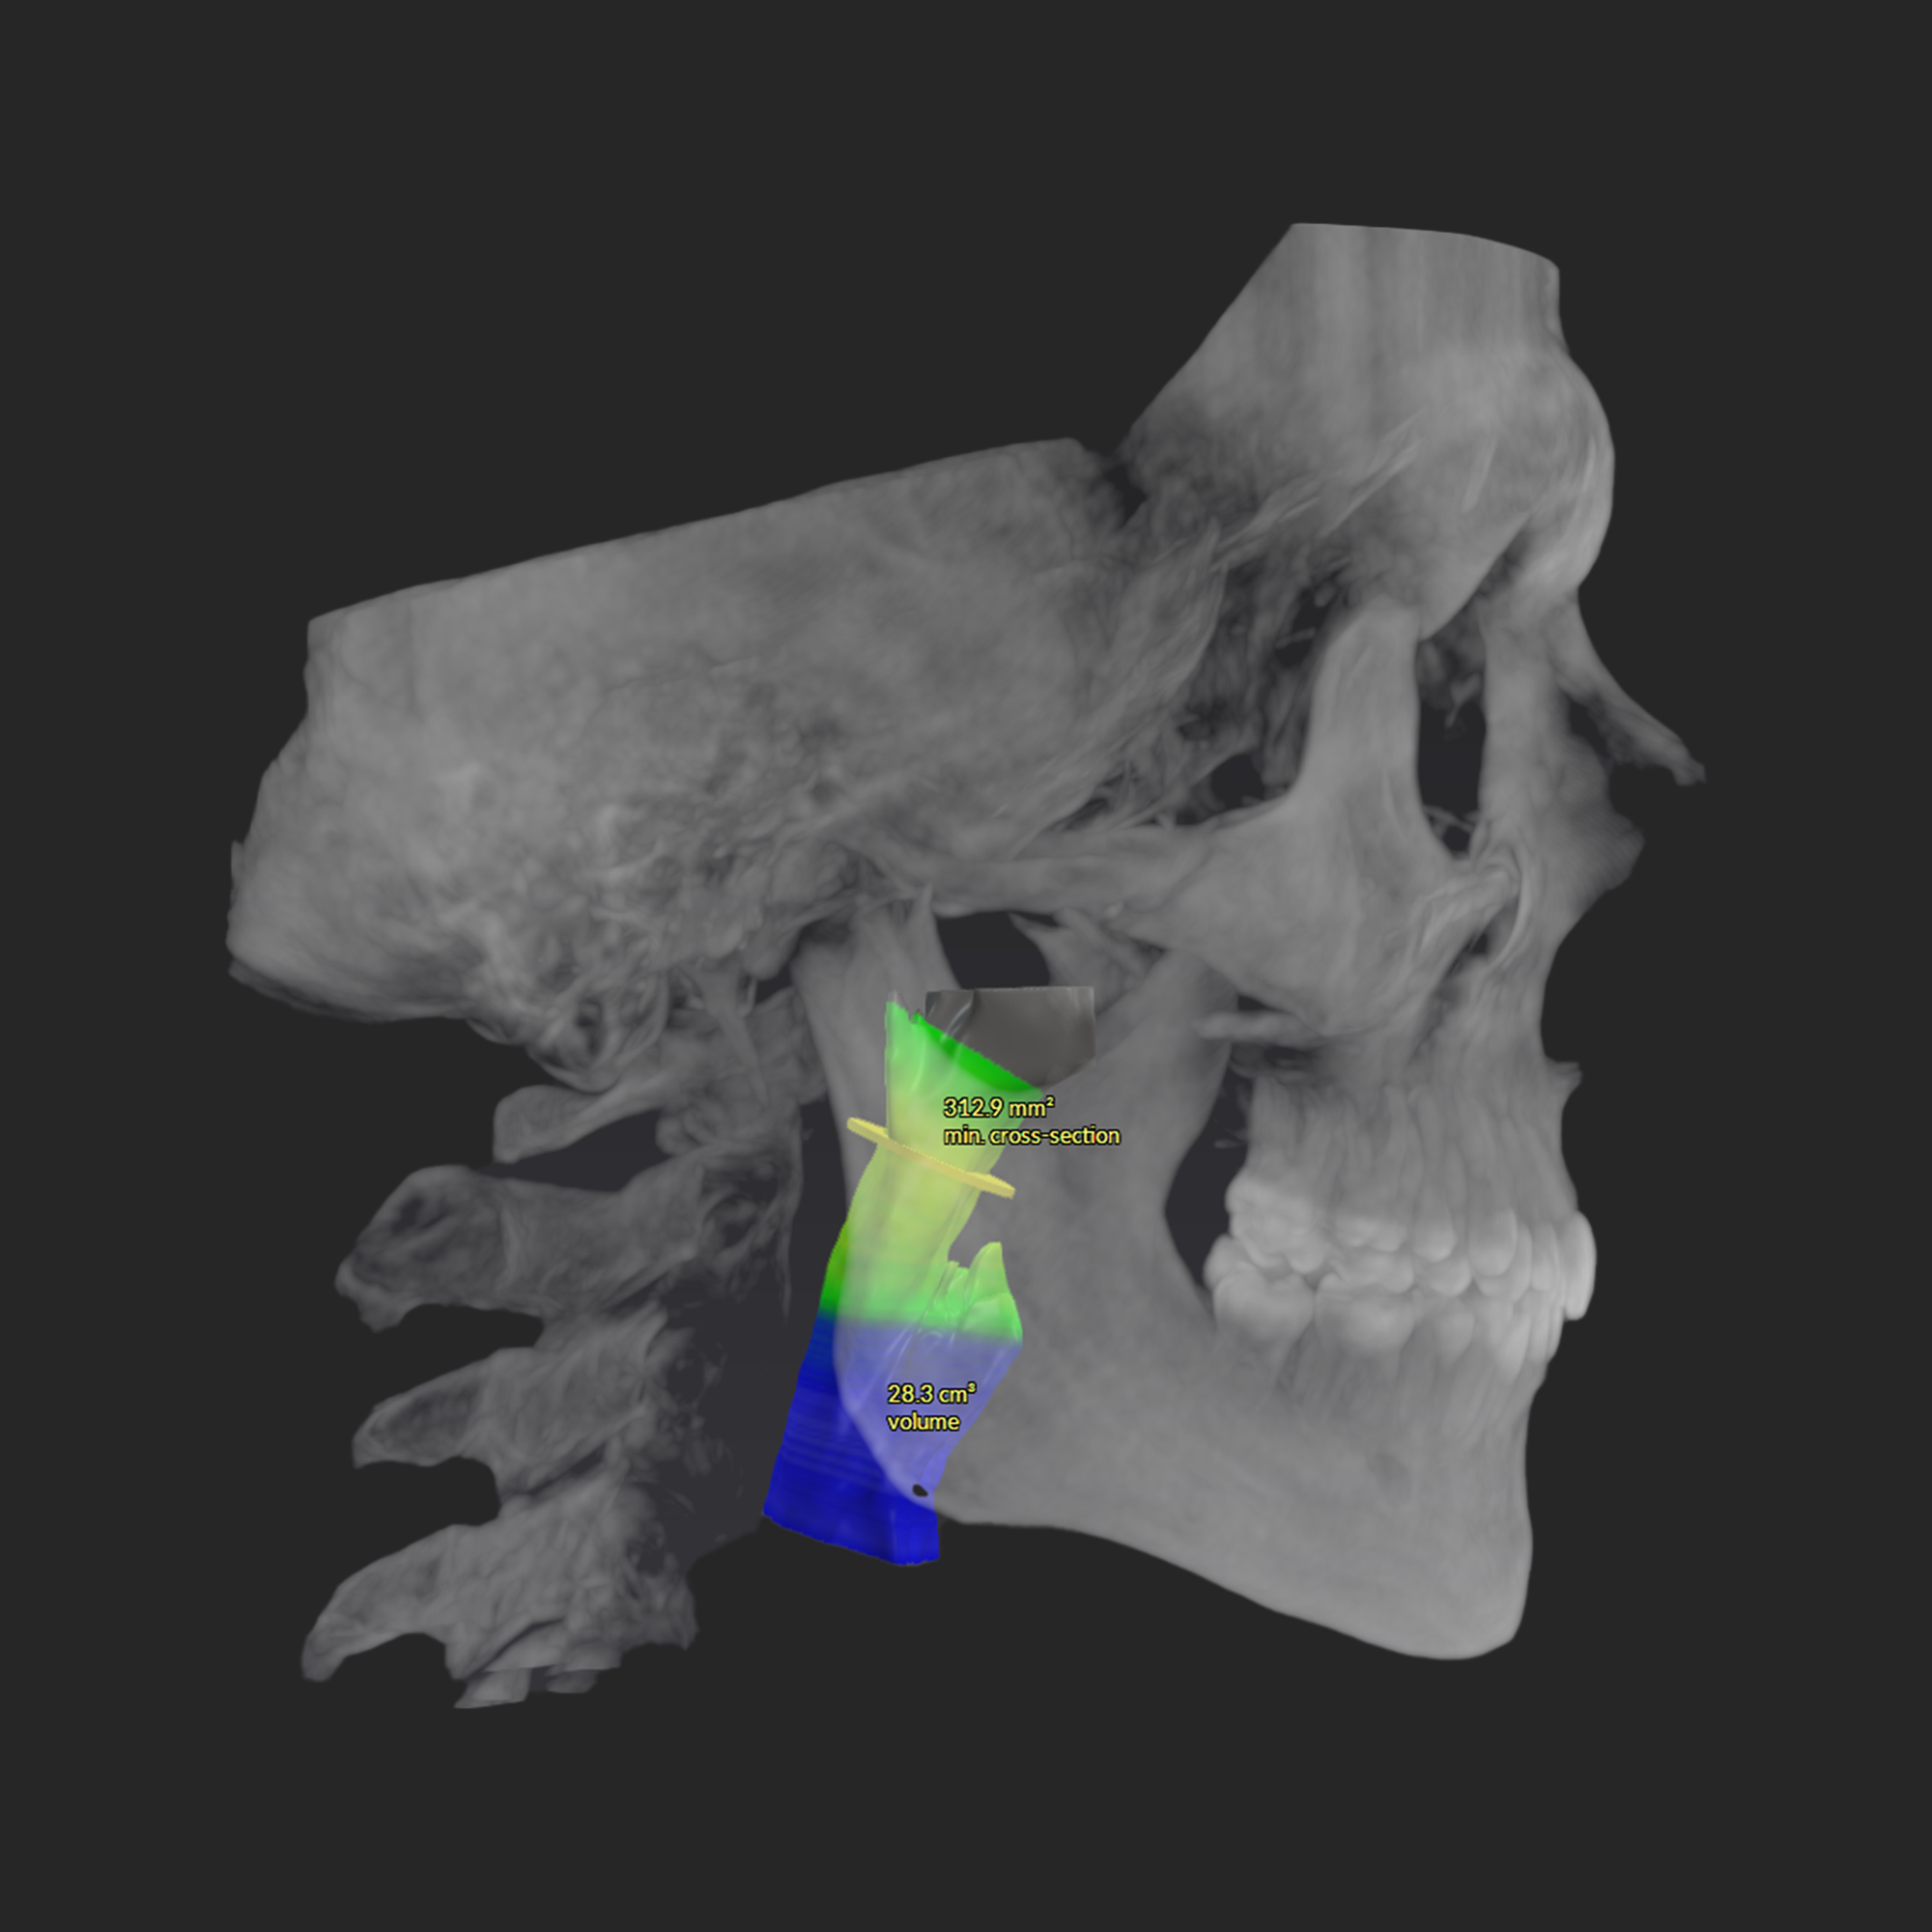

If you struggle with snoring, mouth breathing, poor sleep, fatigue, headaches, grinding, or focus issues, airway diagnostics can help identify root cause. It’s also valuable for children with crowded teeth, narrow arches, or sleep and behavior challenges.

Your evaluation includes a CT scan, comprehensive oral images, sleep assessment, and personalized treatment plan from Dr. Trivedi. If you choose to proceed with the complete solution stack, your evaluation costs will be applied as a discount.

After your evaluation, the doctor reviews your results and explains how your airway structures are impacting your health. You’ll then receive a personalized plan that may include palatal expansion, aligners, or other therapies to optimize your health.